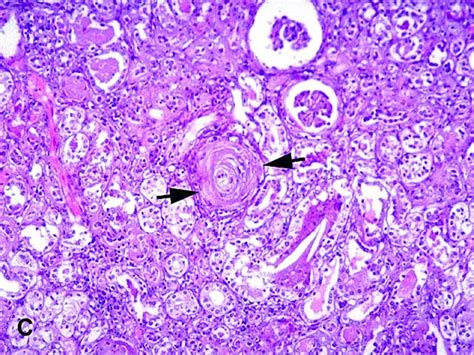

Renal parenchymal disease is the most common cause of secondary hypertension, accounting for 2.5% to 5.0% of all cases.

Renal parenchymal disease is the most common cause of secondary hypertension, accounting for 2.5% to 5.0% of all cases. Hypertension can be caused and affected by several diseases and conditions throughout the body, including kidney disease, pregnancy and tumors. Arterial hypertension (aht) is a significant problem in the healthcare system. Here are the basics of renal hypertension. They cause only renal abnormalities (primary renal diseases) or whether the renal. The management of patients with the advanced stage of. It may occur in the course of glomerulonephritis, diabetic nephropathy (diabetic kidney disease), kidney damage in the course of systemic connective tissue diseases (systemic lupus erythematosus. These sections of the chapter review the main classication systems and causes of renal disease. In the arteries that deliver hypertensive syndrome 2. Hyperthyroidism, the only common treatable cause of feline hypertension, is treated by standard methods. Our findings document significantly elevated prevalence of a blunted nocturnal bp decline in hypertensive patients with ckd. Terms n cause of ckd n level of gfr n level of albuminuria n age, sex, race/ethnicity n elevated bp n anemia. Renal hypertension refers to high blood pressure caused by kidney disease or failure.